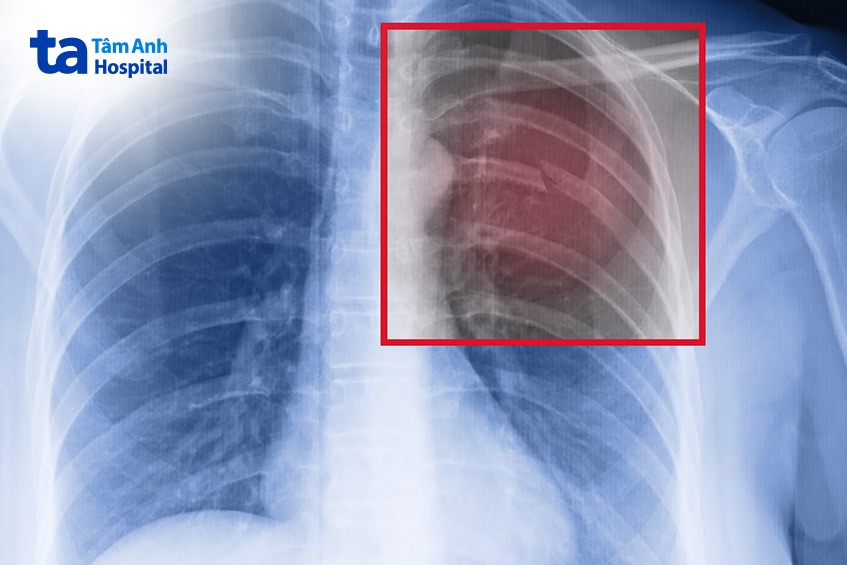

Đây là biến chứng phổ biến và nghiêm trọng của bệnh. Khi virus hoặc vi khuẩn xâm nhập vào phổi qua đường hô hấp. Trong quá trình nhiễm trùng các mô phổi bị viêm nhiễm gây ra tình trạng sưng tấy, phù nề, điều này làm giảm khả năng trao đổi khí gây ra hiện tượng sốt cao, ho nhiều đau ngực và khó thở. Viêm phổi do ho gà thường biến chứng nhanh và có thể dẫn đến suy hô hấp hoặc nhiễm trùng máu đe dọa tính mạng của người bệnh.